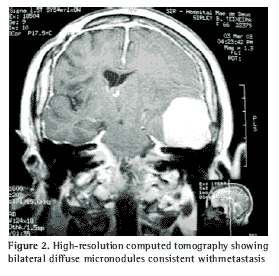

Simple radiogram of the thorax presented diffuse reticulonodular interstitial infiltrate. High-resolution computed tomography of the thorax (Figure 2) revealed micronodules disseminated through both lungs.

Pulmonary metastases from meningiomas typically present as a single lesion, or, less frequently, as multiple noncalcified nodules of different sizes(9), which makes the present case even more rare. The presence of respiratory symptoms in our patient may be explained by the extent of the pulmonary involvement, since our patient presented a restrictive functional profile, as well as a significant change in measurement of pulmonary diffusing capacity for carbon monoxide and no concomitance with another respiratory disease.